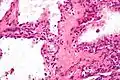

Micrografía mostrando un cistoadenoma seroso del páncreas. H&E stain.